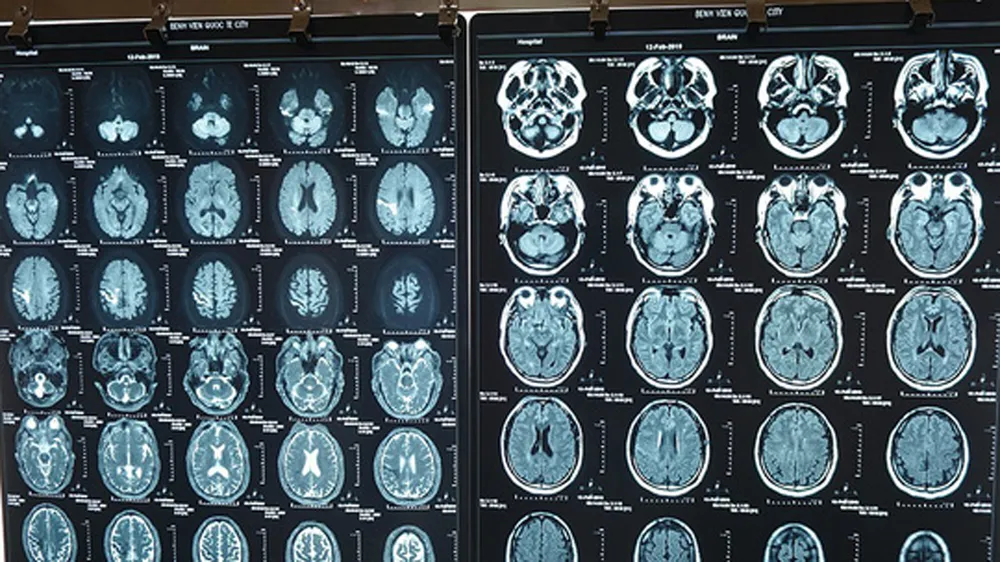

Tại đây, sau khi tổng hợp dữ liệu lâm sàng và chụp MRI sọ não, bệnh nhân được chẩn đoán nhồi máu não cấp giờ thứ 5. Sau phiên hội chẩn liên khoa, các bác sĩ đã quyết định điều trị thuốc tiêu sợi huyết truyền qua đường tĩnh mạch cho bệnh nhân. Sau một giờ tiêm thuốc, sức cơ của bệnh nhân H. đã hồi phục gần hoàn toàn. Đến nay bệnh nhân có thể đi lại, sinh hoạt, nói chuyện bình thường.